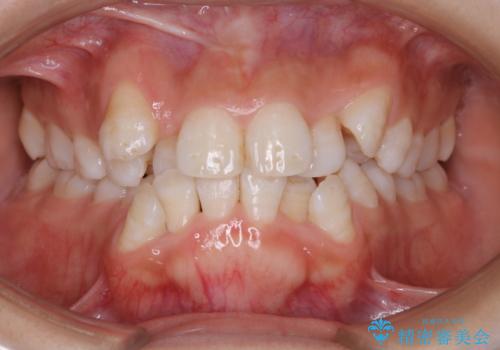

出っ歯と深い噛み合わせ:抜歯矯正で口元スッキリ!

- 出っ歯が気になるとご相談にいらした方です。抜歯して歯を並べました。深かった噛み合わせも改善させることが出来ました。

噛み合わせが元々深い方は一般的に噛む力が強く、治療に時間がかかる傾向にあります。治療前の想定よりも短期間でスムーズに治療を終える事ができ、大変喜んでいただけました。リテーナーによる保定もしっかり行っていただいており、後戻りなく快適にすごして頂けているとのことです。